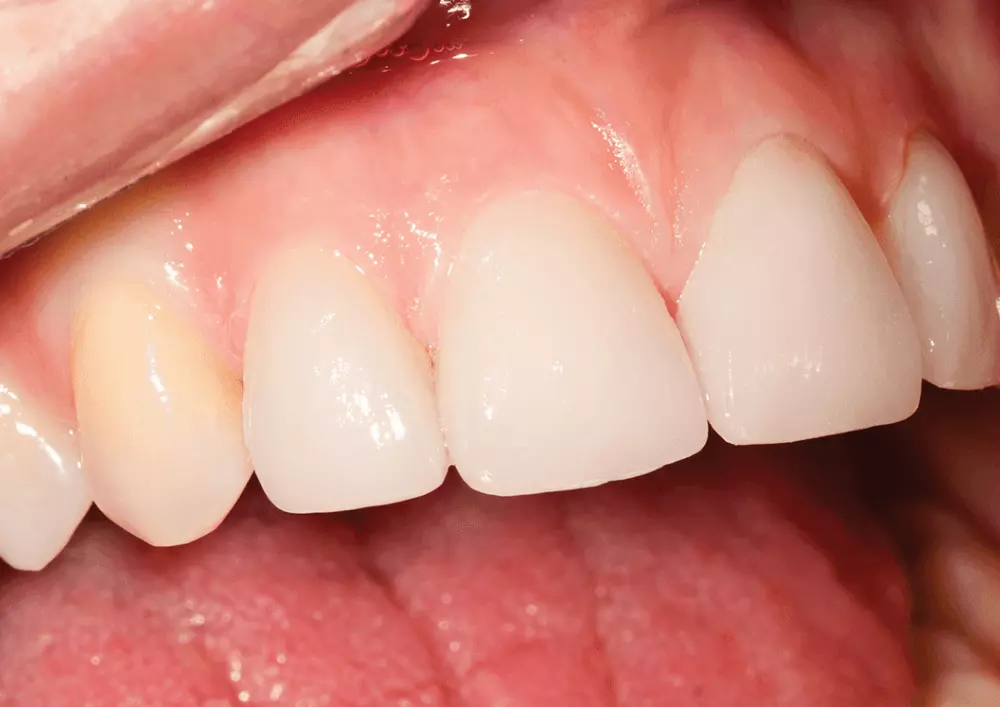

Licówki ceramiczne z wykorzystaniem ceramik szklanych wykonywane są od ponad 20 lat. Charakteryzują się wysoką wytrzymałością mechaniczną. Zapewniają także bardzo dobry efekt funkcjonalny i estetyczny. Przypadek kliniczny stosowania ceramik szklanych w wykonywaniu licówek opisuje dr n. med. Piotr Okoński.